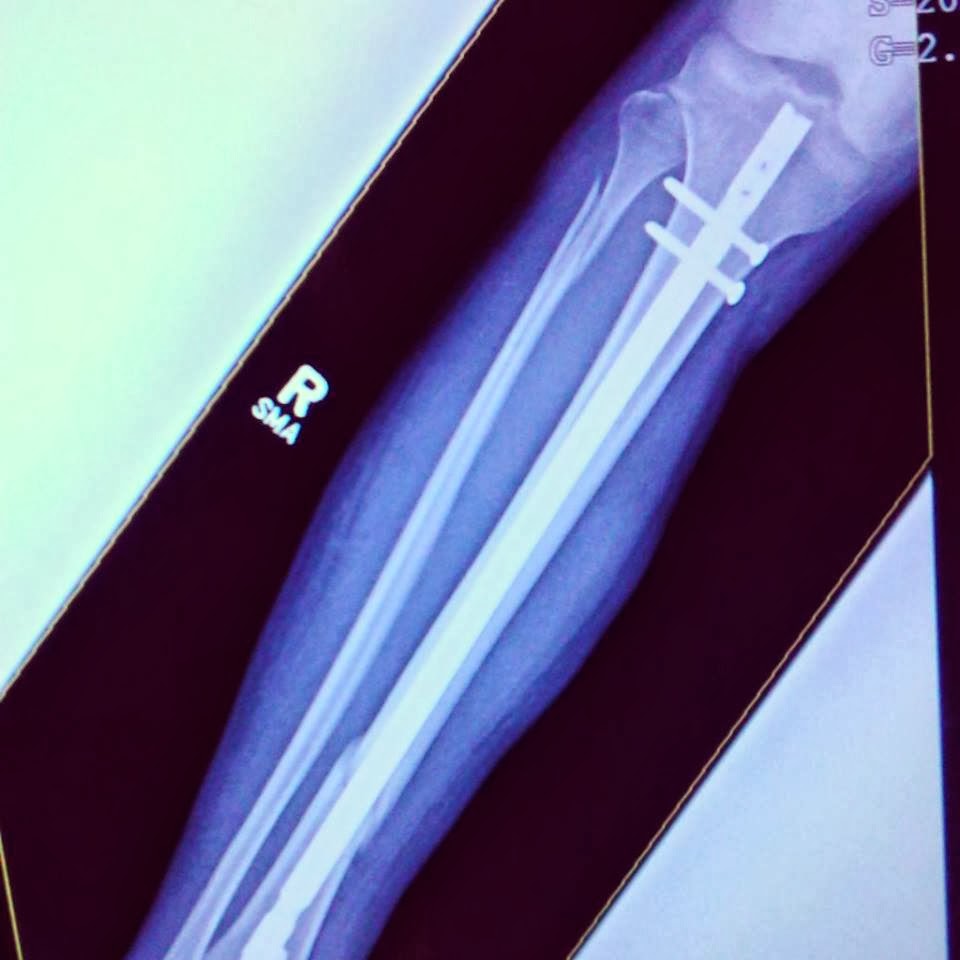

Being rendered essentially immobile by the breaks in his leg, Kendal has been reliant on others to cook meals for him; in particular, Jen. Though I know he is grateful for every bite (he has an unparalleled gift of gratitude), I also know it can be tiring to be the person stuck cooking and cleaning every day.

While they ate, we shared stories from our Thanksgivings. I found my mind wandering, taking note of the number of doorways and people in sight, again wondering what I'd do if there were an earthquake. My thoughts were jolted back to the present when Kendal began to catch us up on the state of his leg. He'd just gotten X-rays and a new cast, so we were eager to hear of his progress.

Turned out, there had been no progress.

Not slight progress. Not mediocre progress.

None.

Despite all the healing I could have sworn Jesus and I were giving, after a solid month of rest and immobility, there was no visible improvement to speak of. His leg was exactly the same.